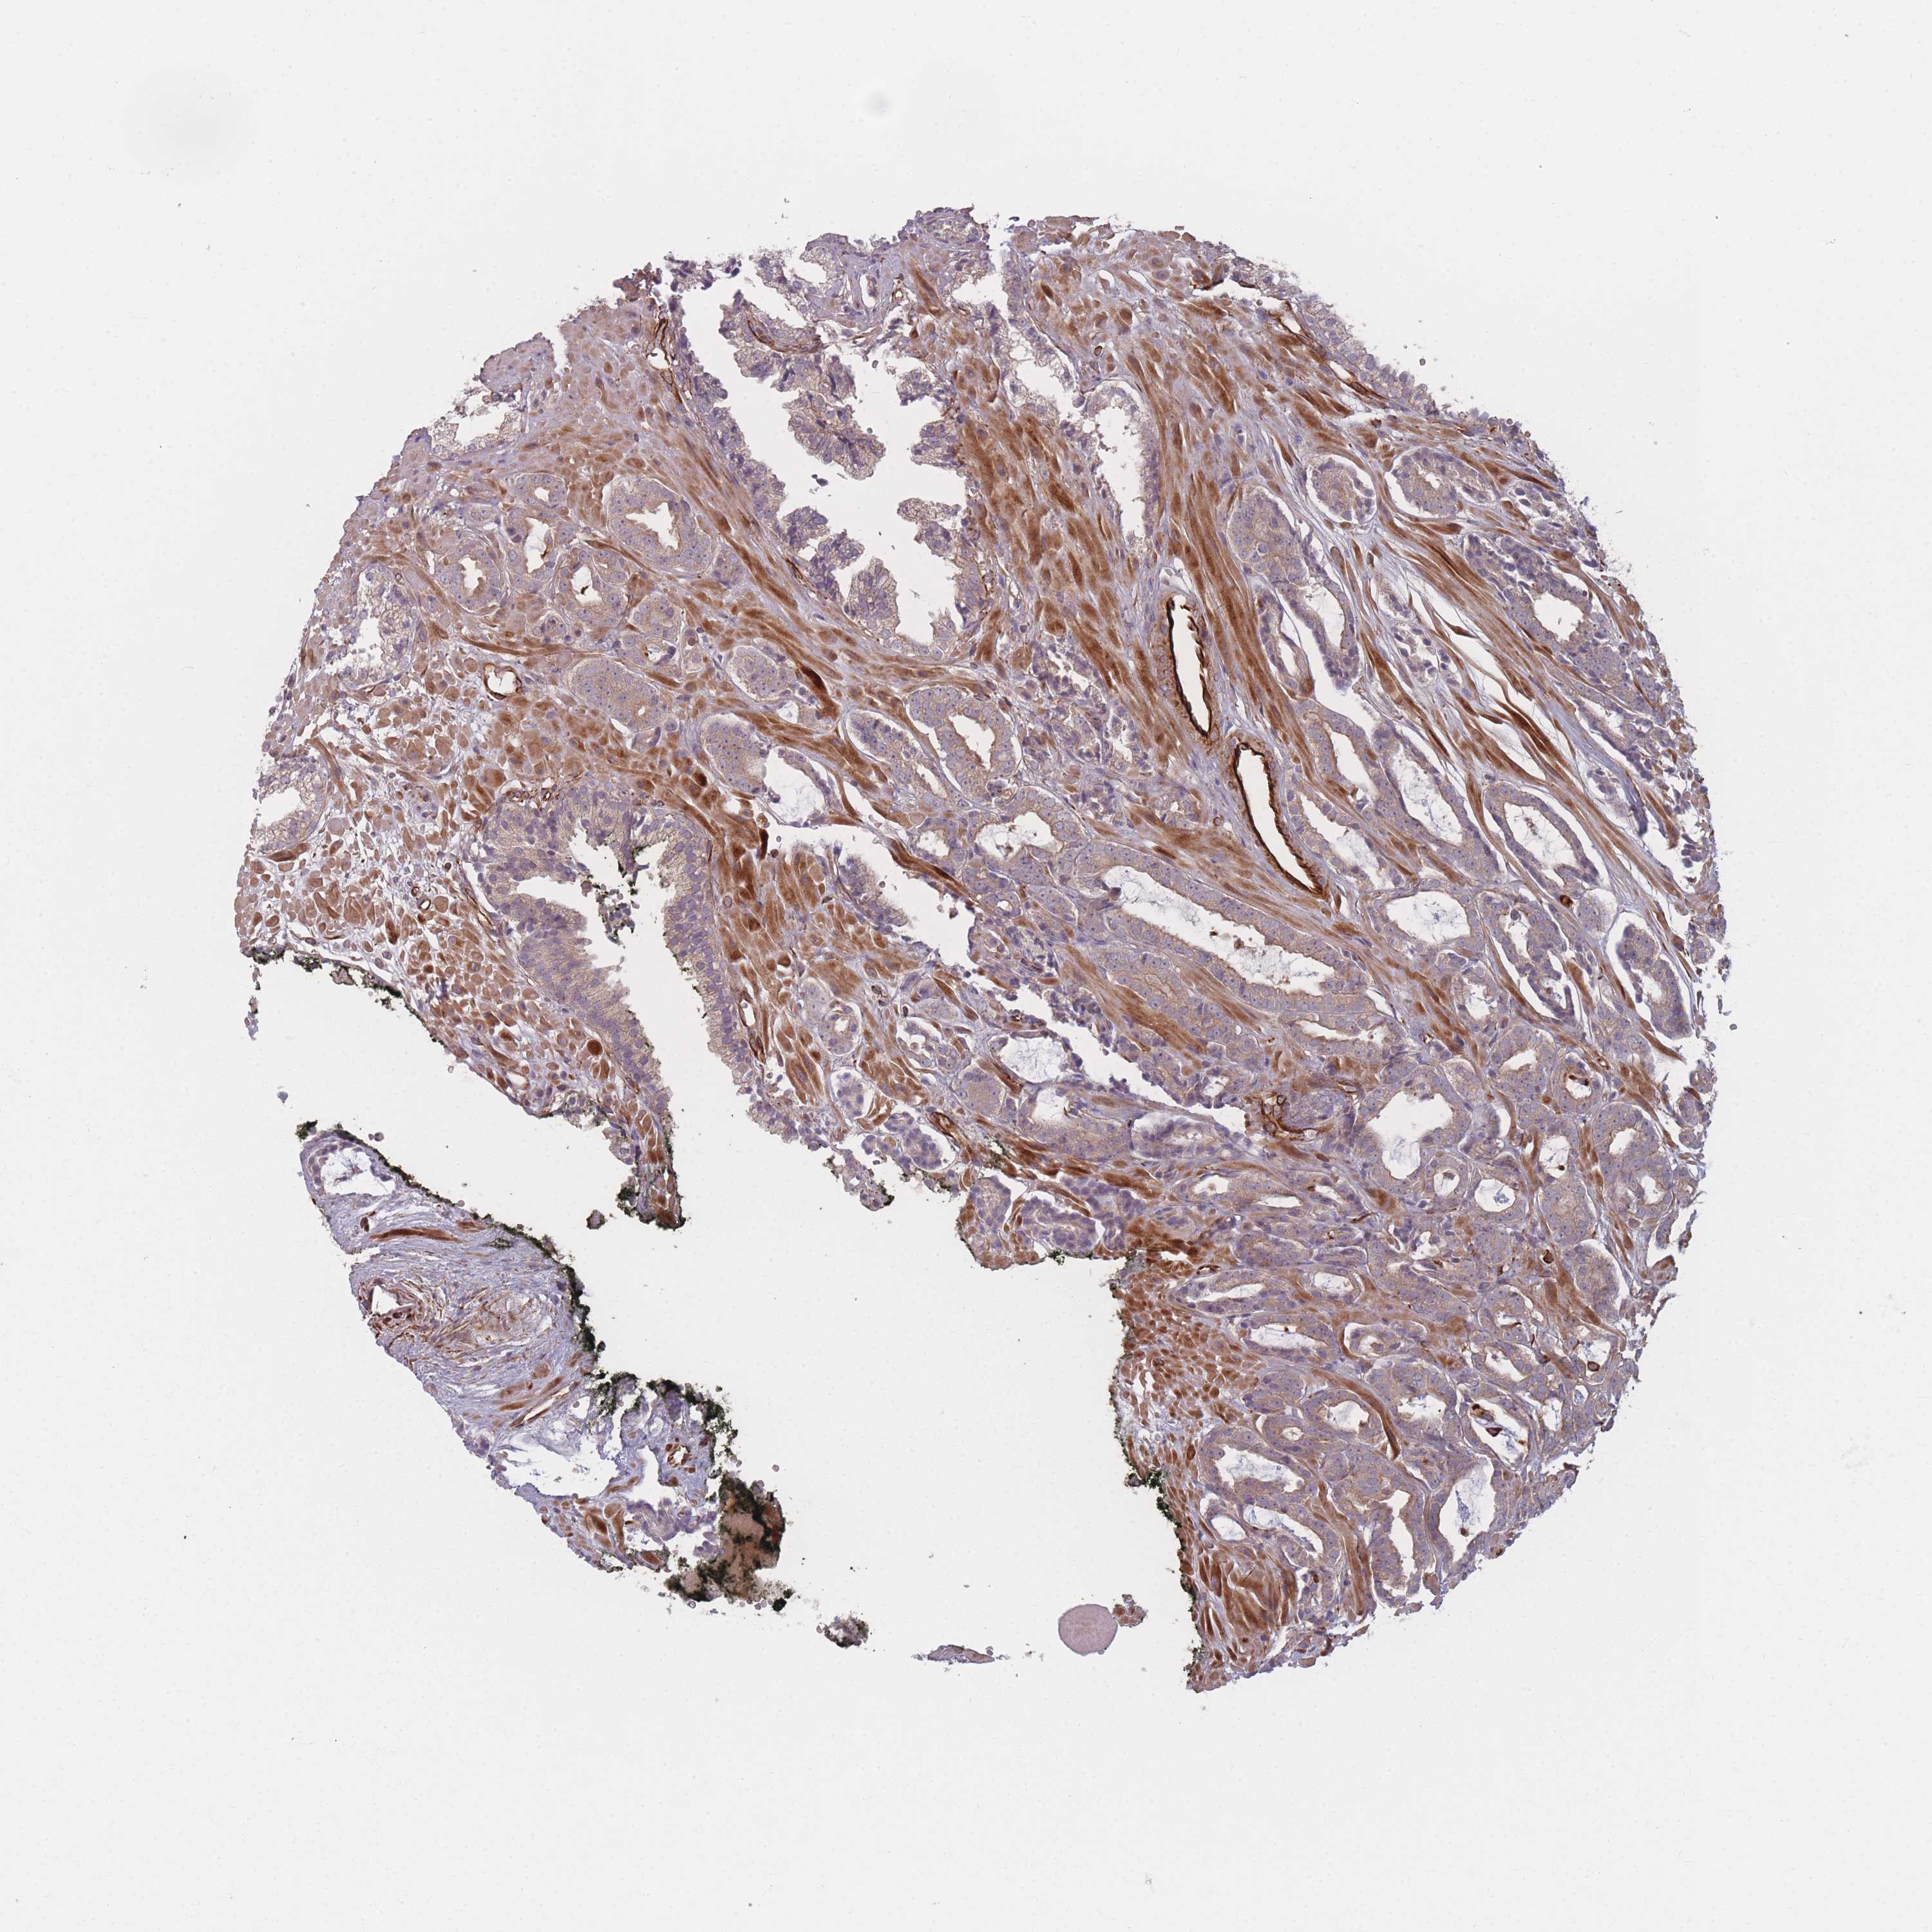

PROSTATE CANCER - Protein expressioni

A mouse-over function shows sample information and annotation data. Click on an image to view it in a full screen mode. Samples can be filtered based on level of antibody staining by selecting one or several of the following categories: high, medium, low and not detected. The assay and annotation is described here.

Note that samples used for immunohistochemistry by the Human Protein Atlas do not correspond to samples in the TCGA dataset.

Antibody stainingi

Antibody staining in the annotated cell types in the current human tissue is reported as not detected, low, medium, or high, based on conventional immunohistochemistry profiling in selected tissues. This score is based on the combination of the staining intensity and fraction of stained cells.

Each image is clickable and will lead to virtual microscopy that enables deeper exploration of all samples and also displays staining intensity scores, fraction scores and subcellular localization as well as patient and tissue information for each sample.

Antibody HPA050138

Staining

High

Medium

Low

Not detected

Intensity

Strong

Moderate

Weak

Negative

Quantity

>75%

75%-25%

<25%

None

Location

Nuclear

Cytoplasmic/membranous

Cytoplasmic/membranous,nuclear

Adenocarcinoma, High grade

Adenocarcinoma, Low grade